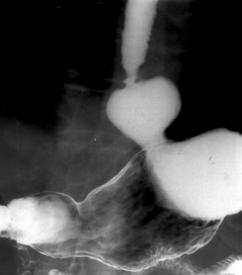

Fig. 13: Pneumonie pneumococica - opacitatiede intensitate medie, omogena cu bronhograma aerica, imprecis delimitata, de forma triunghiulara cu varful la hil.

Fig. 14 – Pneumonie lobara superioara dreapta in rezolutie (opacitate sistematizata neomogena, de intensitate mica spre medie, delimitata inferior de mica scizura, ocupand LSD)